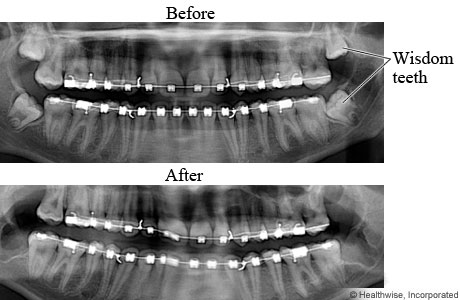

Wisdom teeth X-ray

X-rays of teeth before and after wisdom teeth removal

Wisdom teeth are the upper and lower third molars, located at the very back of the mouth. In some people, wisdom teeth are crowded and difficult to clean properly. They may also push against other teeth. In the "After" image, the wisdom teeth have been extracted (removed).